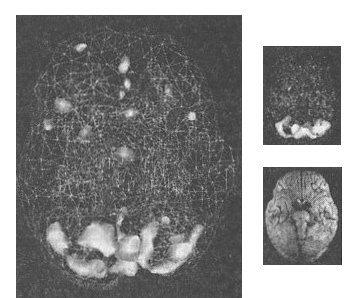

В качестве элемента контроля мы трижды делали скан мозга Стивена: до лечения, во время первой сессии с Сарой и после восьми часов терапии ДДГР.

Изначально томограмма Стивена показала классический рисунок посттравматического стрессового расстройства с крайней гиперактивностью лимбической системы. Затем за работу взялась Сара, по одной вычищая травмы из памяти. Мозг показал улучшения уже во время первого сеанса, а всего через восемь часов значительно исцелился. Тремор прошел, Стивен стал лучше себя чувствовать. Сара рассказала мне, что в процессе терапии Стивен стал приходить к прощению своего отца и поинтересовался, как мог выглядеть мозг его отца. До этого в его отношении к отцу присутствовала только ненависть, но работа с мозгом дала Стивену новую перспективу. Когда мы с Сарой помогли ему сбалансировать мозг, улучшилась вся его жизнь.